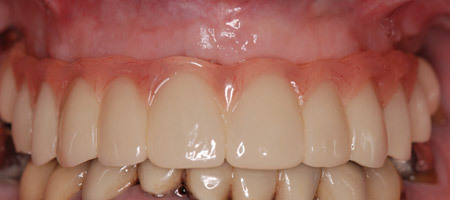

Le bridge provisoire (juste avant la confection du bridge d’usage).

Le bridge provisoire (vue du sourire)

La gencive est parfaitement saine au moment de la confection du bridge d’usage.

Le bridge d’usage en zircone est usiné après essayage d’une maquette esthétique.

Vue externe du bridge d’usage au repos.

Aspect intra-oral du bridge d’usage. Le passage des brossettes est vérifié et un brossettogramme est remis à la patiente.